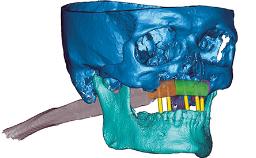

Rehabilitating an Edentulous Maxilla with Three Separate Bridges

A 55-year-old woman was referred to our clinic for implant therapy. She was healthy and had stopped smoking two years previously. Ten years before, the patient had received extensive dental treatment in both jaws. The patient reported that her dental condition had deteriorated progressively since that time. At the time of presentation, the maxillary bridge was loose. The clinical and radiographic examinations revealed a highly compromised situation for all the teeth that supported the bridge and for other teeth.

| # of Implants | 8 |

| Type of Implants | Reduced-Diameter|Two-Piece |

| Bone Augmentation | Horizontal|Simultaneous |

| Guided Surgery | Yes |

| Bone Volume | Deficient horizontally, allowing simultaneous augumentation |